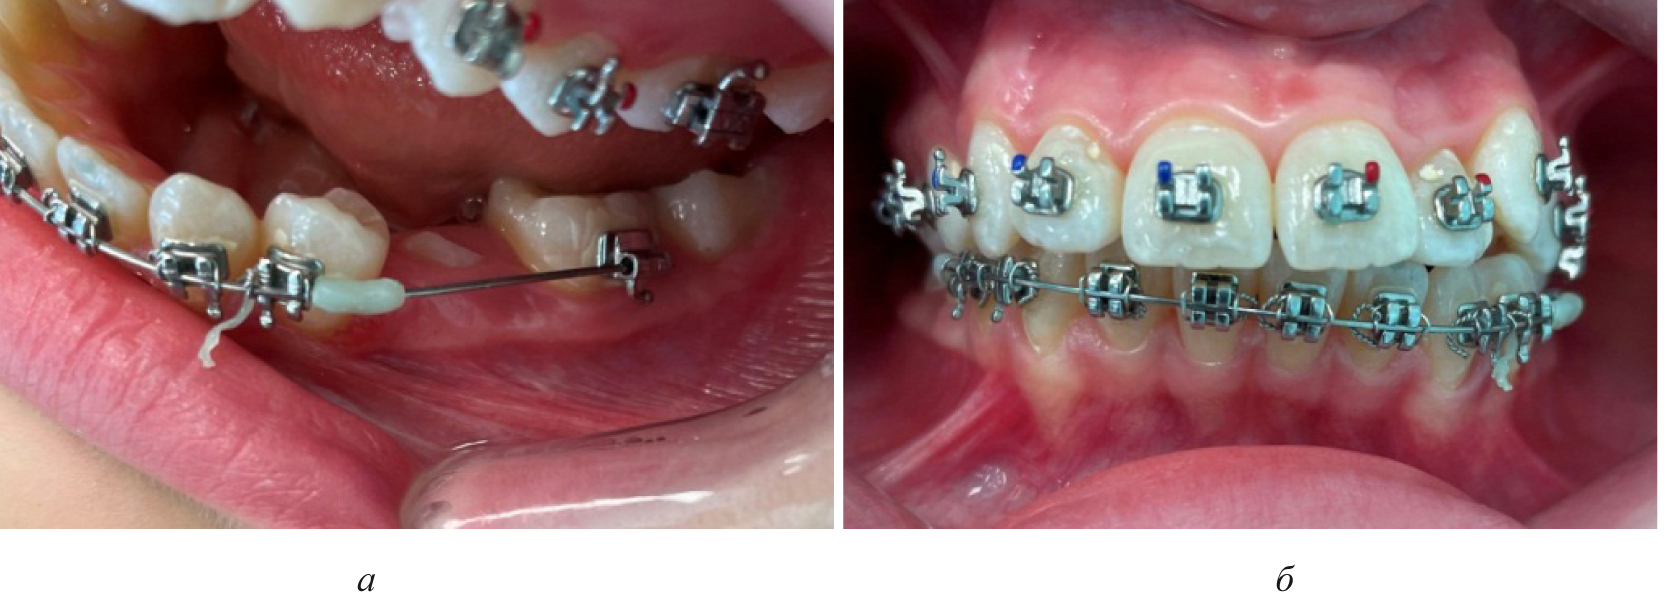

Лечение пациентов, как правило, проводилось с использованием несъемной ортодонтической аппаратуры, в частности эджуайс-механикой.

На первом этапе проводилось раскрытие пространства в области ретенированного зуба и создания условий для его прорезывания. После этого устанавливались элементы аппарата на противоположной челюсти (рис. 4).

Последующие этапы ортодонтического лечения техникой эджуайс проводились с учетом общепринятого протокола и этапности смены металлических дуг, что способствовало нормализации окклюзионных взаимоотношений (рис. 5).

Рис. 3. Окклюзионные взаимоотношения справа (а), спереди (б) и слева (в) у пациента с односторонней ретенцией второго премоляра

Рис. 4. Создано место для прорезывания премоляра (а), установлена аппаратура на верхнюю челюсть (б)

Рис. 5. Окклюзионные взаимоотношения справа (а), спереди (б) и слева (в) на завершающем этапе лечения